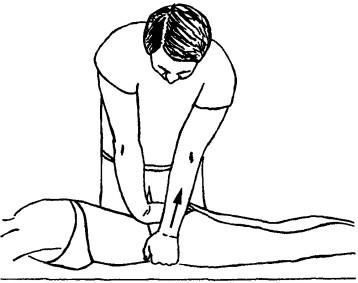

Ábra. 150. mobilizálása sacroiliacalis közös ventrodorsalnogo ellensúlyozza a csípő a helyzetben a beteg hátán fekszik

Mobilizálása ventrodorsalnogo elmozdulás a hanyatt fekvő helyzetben. A beteg a hátán fekszik, az egyik láb egyenes, és az oldalán a mozgósítás - behajlítva a térd és a csípő. Az orvos, feküdt a másik oldalon a hajlított láb, megragadja, és adja meg, amíg a medence elkezd forogni után a láb és amíg az orvos fogja érezni az előfeszítő. Elmozdulás, hogy a csípő a zárolt oldalán kisebb, mint az egészséges. Az ujjak a másik viszont alatt találhatók a hátsó és a keresztcsonti gerinc (ábra. 150). Az orvos ezután elvégzi álljon át a combcsont a térd tengely irányában hátsó csípőnyerge. „Jog” kar érzi ellenáll a nyomásnak a térd és a másik tapintással értékeli ugrott a csípő képest a keresztcsont, és felhívja a figyelmet, hogy a jelenléte fájdalom ezeket a mozgásokat. Mozgástartomány és érzékenység sacroiliacális ízületek összehasonlítjuk a két fél.